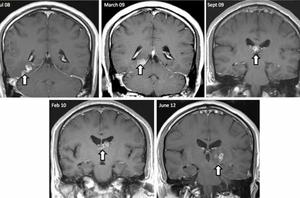

استعمال قلیان، عامل مهم بروز سکته مغزی است

مصاحبه اختصاصی: مواجهه با سکته مغزی از زبان متخصص مغز و اعصاب

سکته مغزی